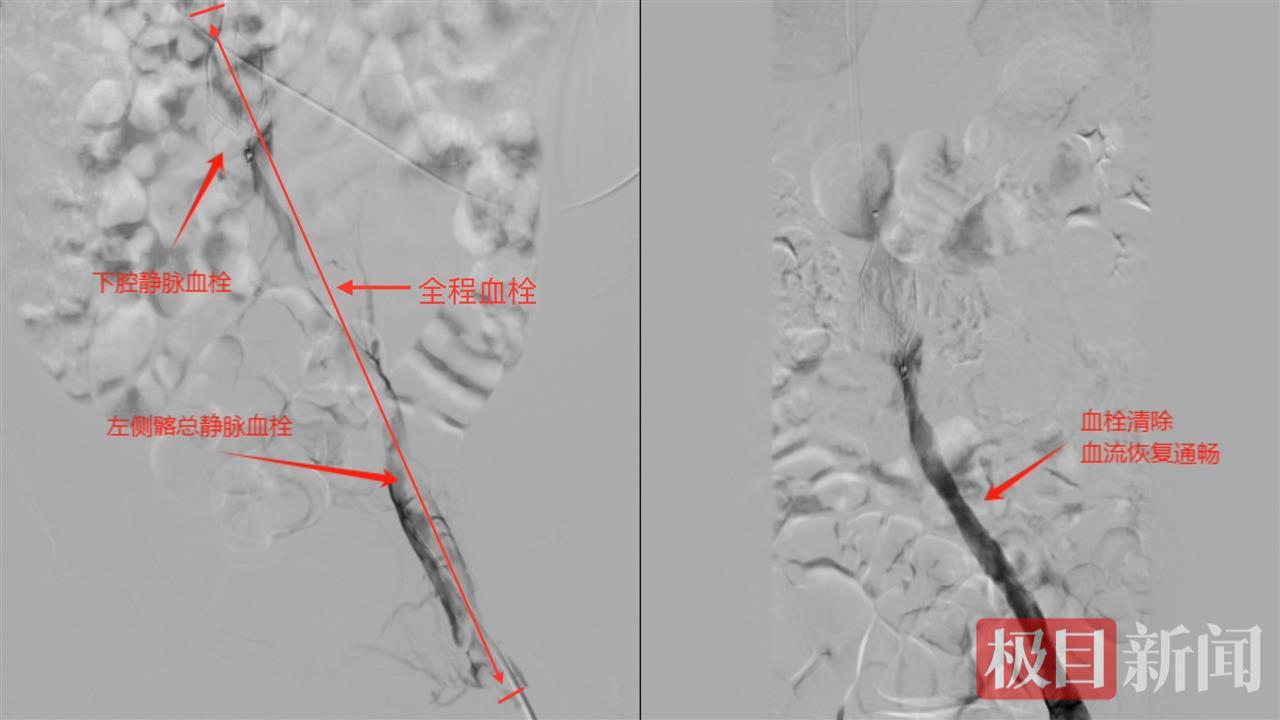

此时,兰先生的病情十分危急,同时存在双肺多发肺栓塞、下腔静脉血栓形成、双侧髂静脉血栓形成、左下肢深静脉血栓形成,随时可能因血栓脱落导致肺栓塞加重,严重者甚至会形成致死性肺栓塞而危及生命。李良学主任团队迅速制定了详细的手术方案,决定为兰先生实施经皮DSA下腔静脉取栓术、下腔静脉滤器置入术、经皮下肢静脉取栓术、髂静脉球囊血管成形术、下腔静脉导管溶栓、髂静脉导管溶栓等介入手术。

“该患者手术涉及血管范围广泛,其下腔静脉、髂静脉及下肢深静脉广泛血栓形成且双肺已存在多发肺栓塞及肺梗死,术中操作极易导致血栓脱落引发致死性肺栓塞危及生命,同时血栓累及多部位血管也使得手术处理需更加谨慎。”李良学主任强调道。当晚,经过李良学主任团队的努力,手术最终取得了成功。术后,兰先生恢复情况良好,各项生命体征逐渐平稳。